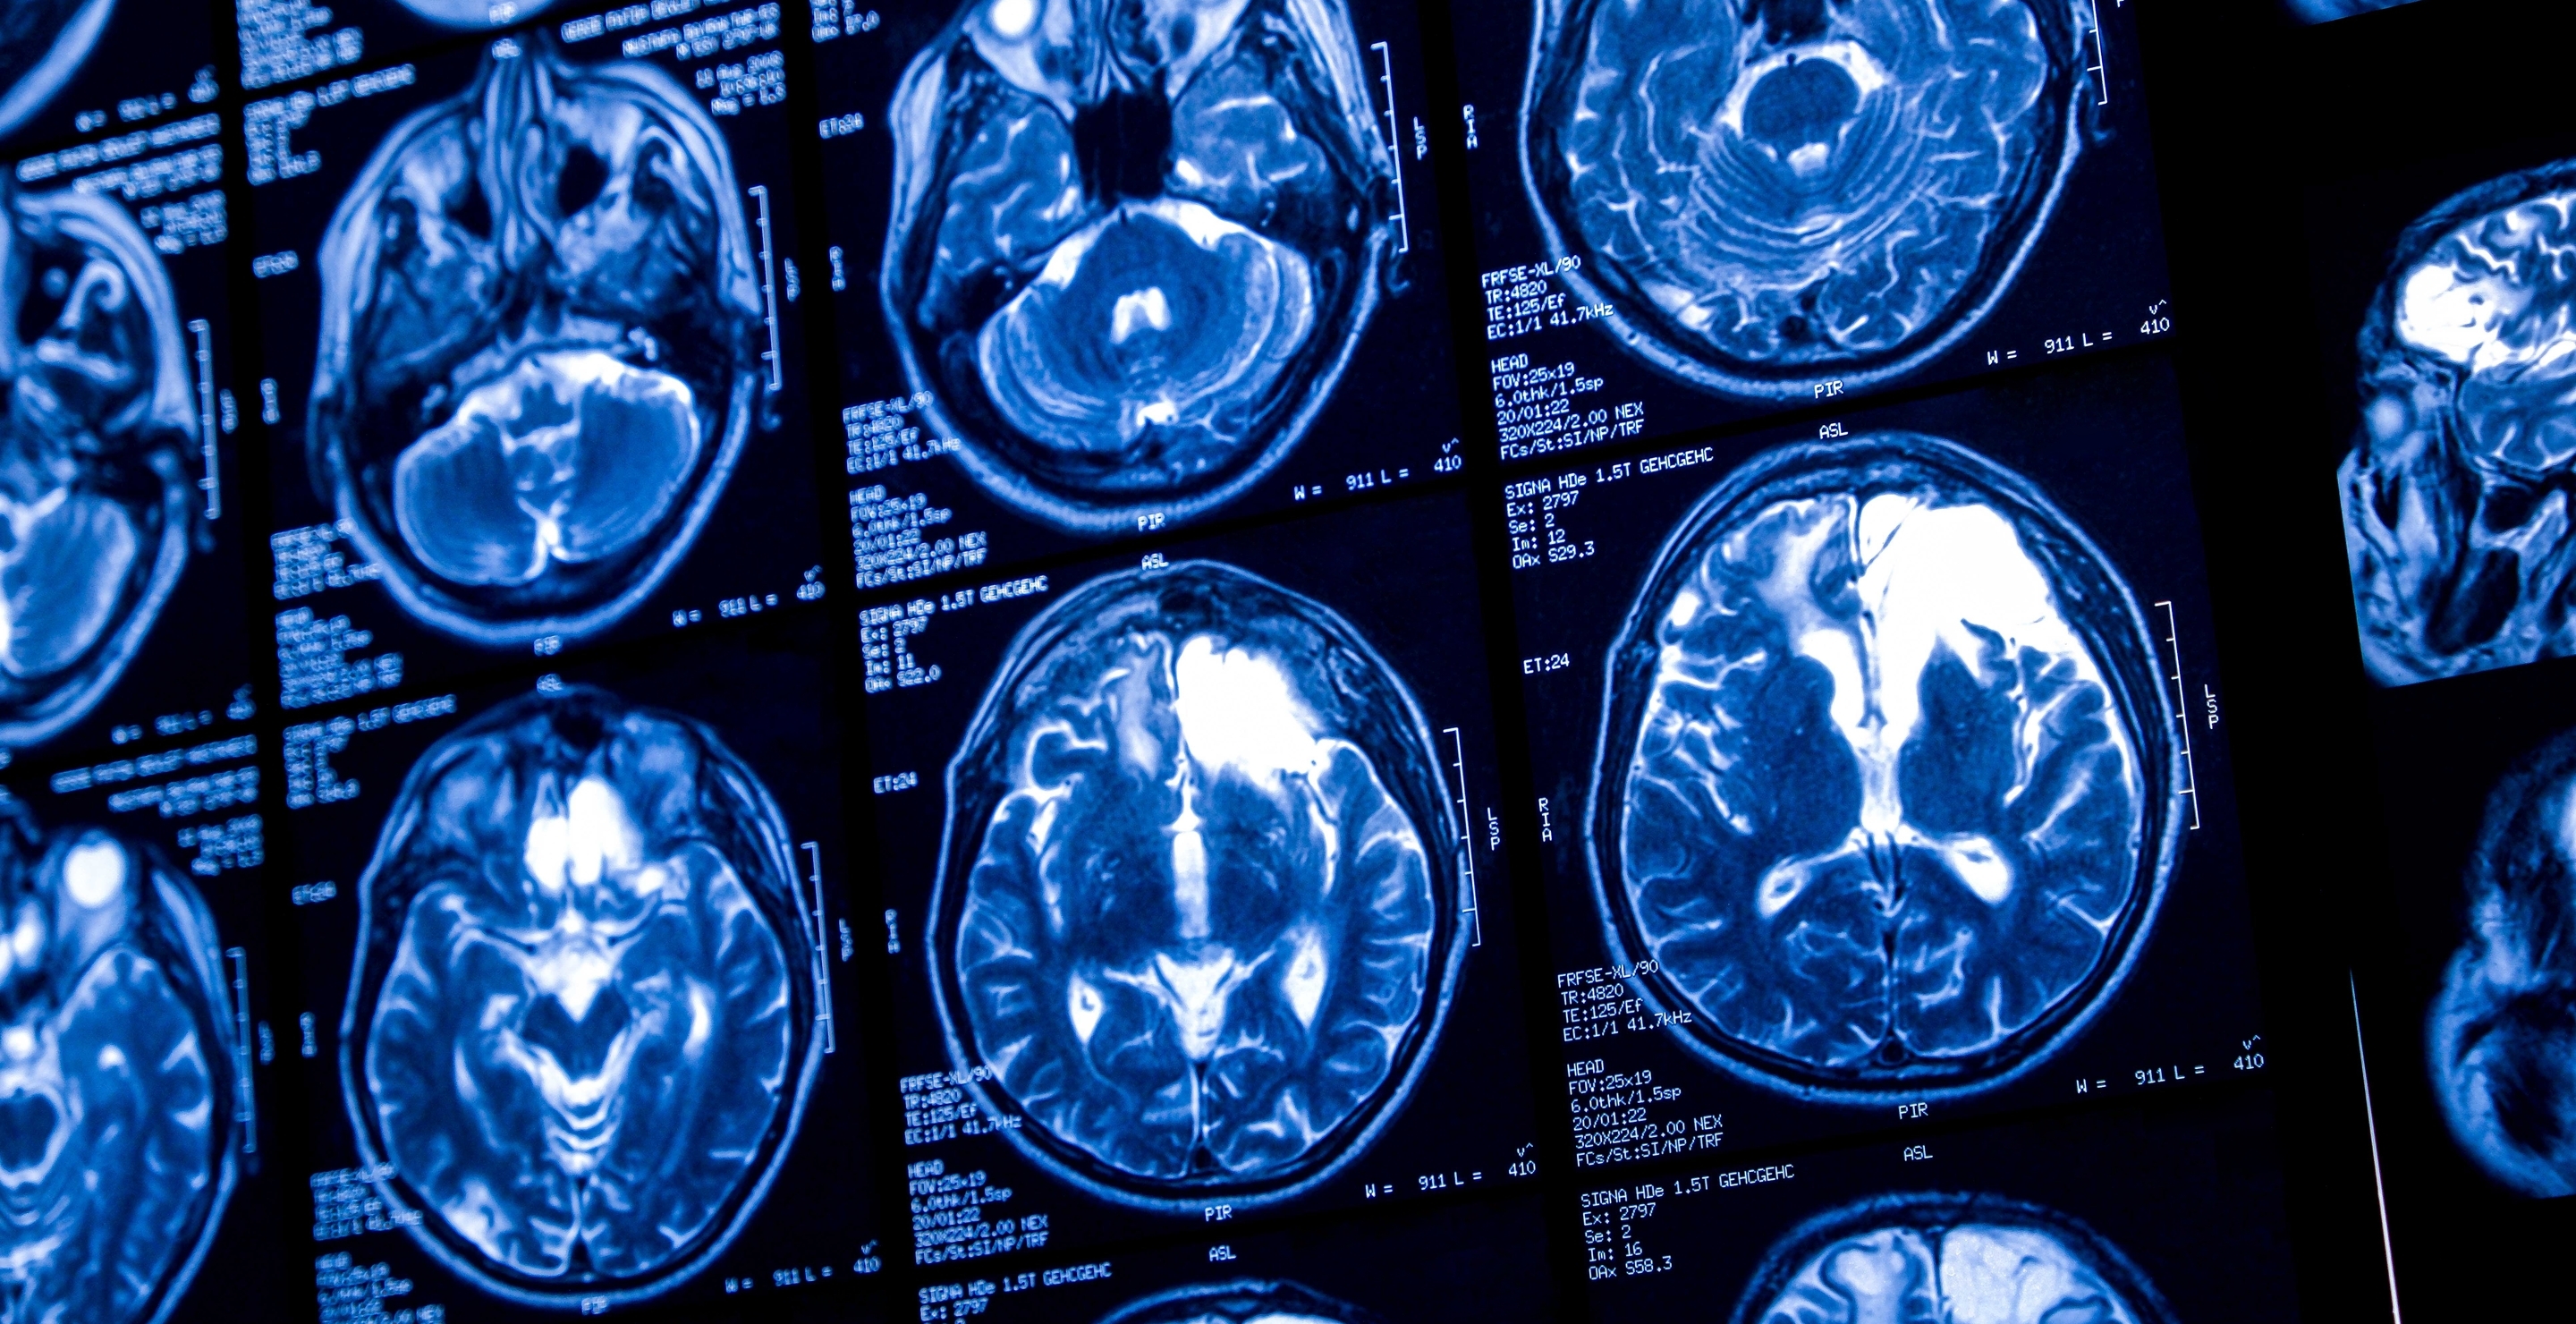

But now, with a simulation video uploaded by The Economist, we can actually see how the brain ages. It has helped explain numerous changes in behaviour and function throughout our lives.